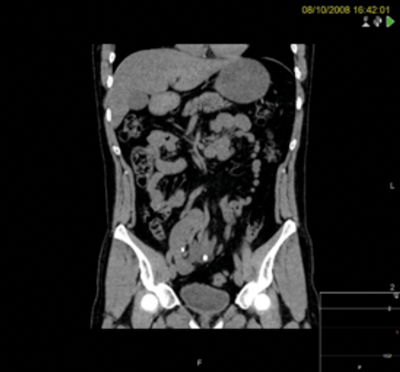

A 37-year-old male presented with stones in a right pelvic kidney. Flexible ureteroscopy demonstrated a tight and very tortuous ureter with no access to the renal pelvis.

PCNL was discussed at a specialist x-ray meeting but considered unsafe due to the risk of perforating overlying bowel.

Figures above demonstrate worsening hydronephrosis preoperatively.

Pre-laparoscopy retrograde examination.